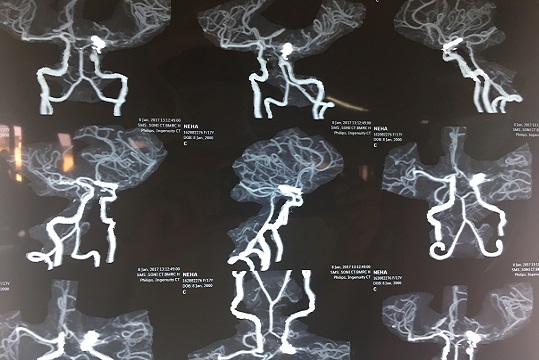

Neurovascular Surgery

Management of aneurysms, arteriovenous malformations, and stroke.